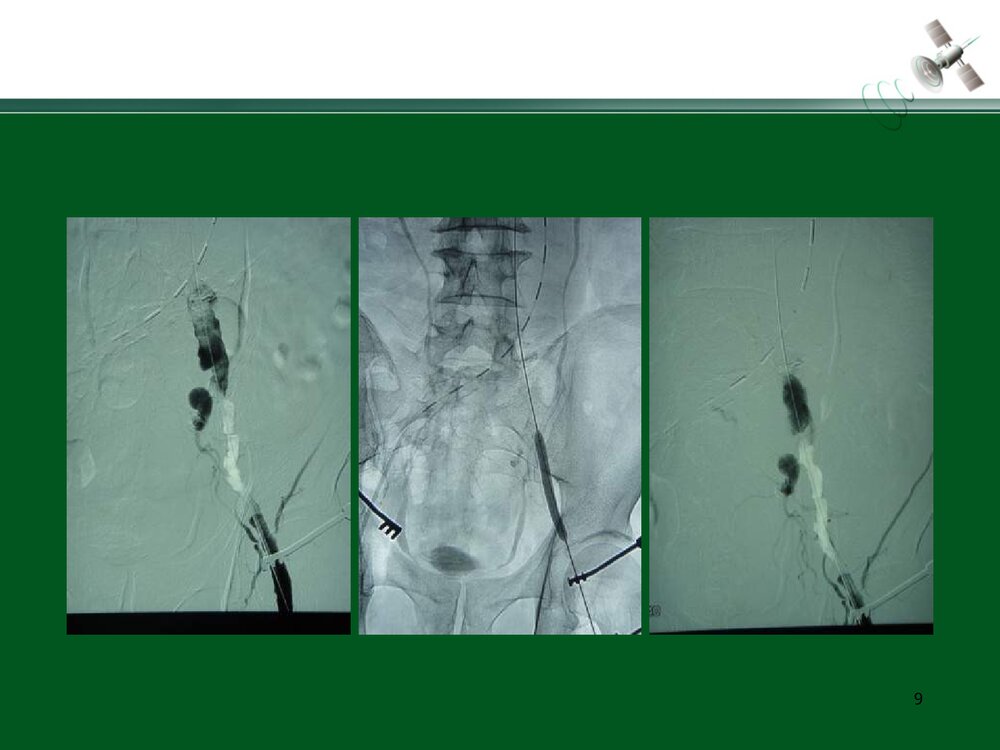

复杂腹主动脉瘤的腔内治疗常光其王深明教育部国家重点学科卫计委国家临床重点专科中山大学附属第一医院血管外科中山大学血管外科研究中心1复杂瘤颈AAA的腔内治疗复杂瘤颈指下列情况1.瘤颈长度小于15mm;2.瘤颈角度大于60度;3.瘤颈直径过大或过小(小于18mm或大于32mm)例1:短瘤颈AAA的EVAR3456例2:短瘤颈伴入路血管狭窄AAA的EVAR7891011例3:瘤颈狭窄且成角大于60度AAA的EVAR12131415161718192021例4:瘤颈成角大于60度AAA的EVAR2223242526例5:瘤颈成角伴腹主动脉分叉狭窄AAA的EVAR272829303132复杂入路AAA的腔内治疗复杂入路是指下列情况:(1)髂动脉弯曲成角超过90°;(2)双侧髂股动脉广泛钙化伴严重狭窄,直径小于7mm;(3)双侧髂股动脉闭塞例6:入路血管严重狭窄AAA的EVAR34353637383940例7:入路血管严重...